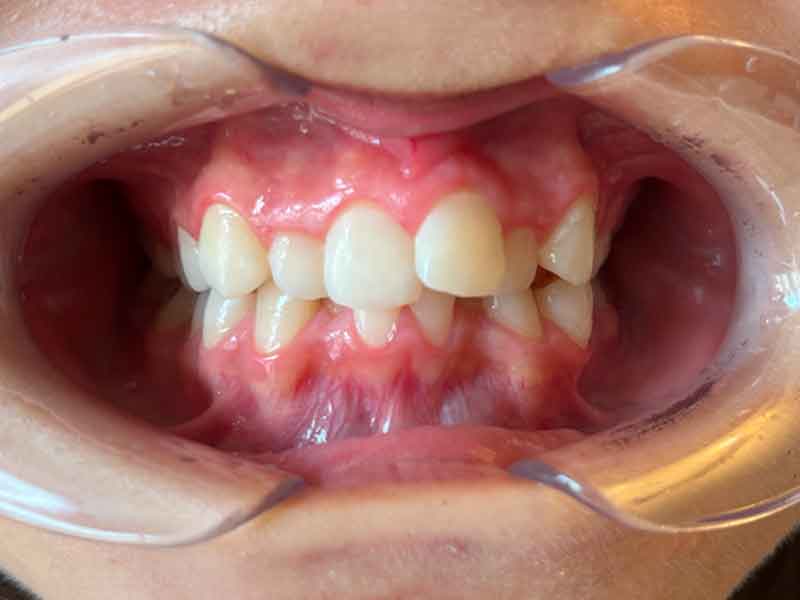

Résultat · Février 2025

En 4 mois — Un résultat visible qui change la trajectoire orthodontique

En seulement 4 mois de port de la plaque d'expansion, la progression est visible et convaincante.

Le décalage de Classe II est atténué : la relation entre les arcades supérieure et inférieure s'est améliorée

La canine supérieure a commencé à trouver sa place dans l'arcade

L'occlusion latérale est plus harmonieuse

Le maxillaire s'est élargi, avec un effet de chaîne positif sur l'ensemble de la relation entre les deux mâchoires

Quatre mois. Un appareil amovible. Un résultat qui change la trajectoire orthodontique de cette patiente pour les années à venir.